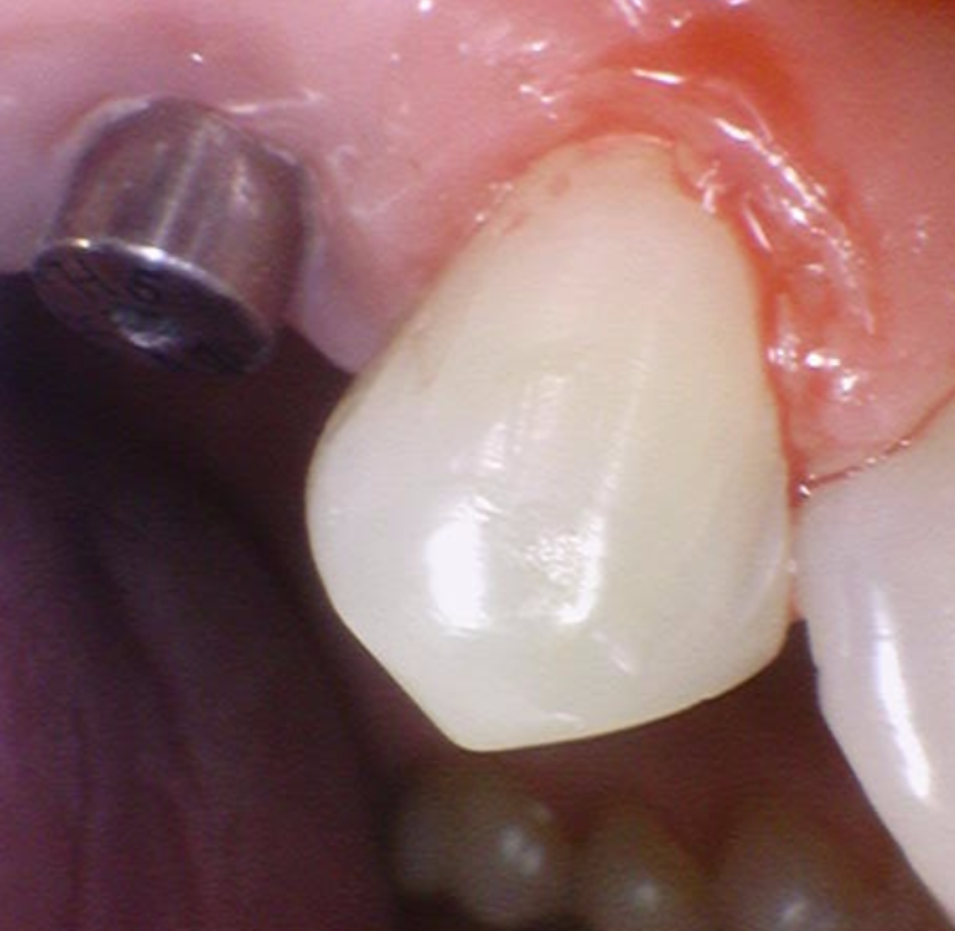

240704 쇠 기둥 아래 임플란트가 숨어져있습니다 .

240930